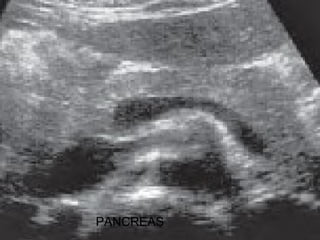

PANCREAS

2.- PLANO DE CORTE:

II.- ESTUDIO DE PANCREAS:(BORDE INFERIOR)